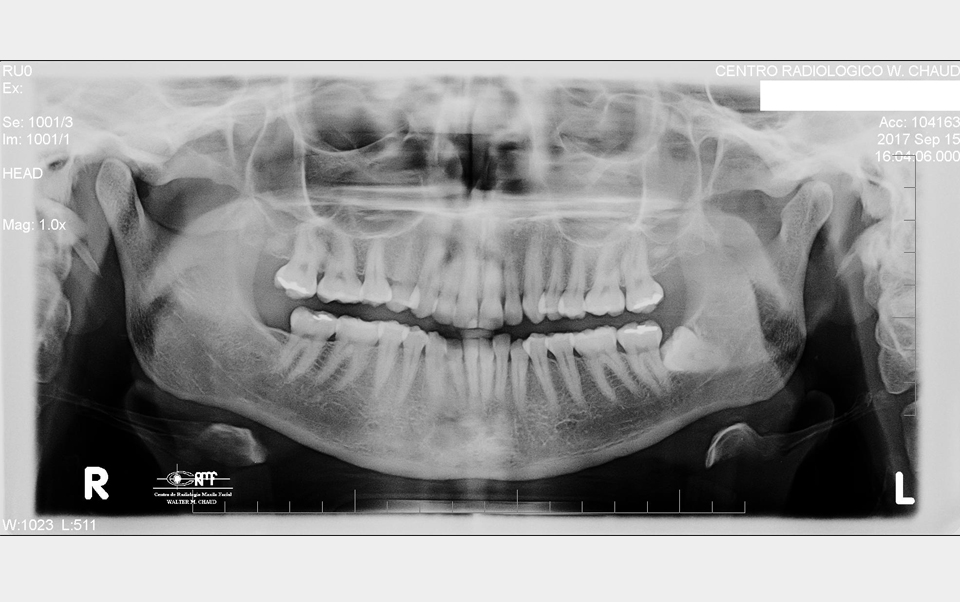

Hoy en día es un estudio rutinario y fundamental en la historia clínica inicial. Es la radiografía extrabucal más utilizada en odontología.

En una sola proyección muestra maxilar superior e inferior. Revela el estado de la dentición de ambos maxilares, tanto la temporal niños) como la permanente (adulta). Provoca una magnificación de la imagen en un 20 – 30 %.